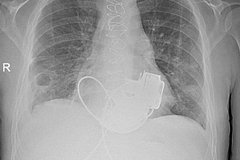

Фото: Комздрав СПб / Telegram

Уникальный пациент без пульса готовится к выписке из петербургской Мариинской больницы. Мужчине впервые в России имплантировали сразу два искусственных желудочка сердца. Об этом рассказали в официальном Telegram-канале городского комитета по здравоохранению.

В итоге главный врач больницы Игорь Реутский принял решение об имплантации не одного, а сразу двух искусственных желудочков сердца, потому что одного прибора было бы недостаточно.